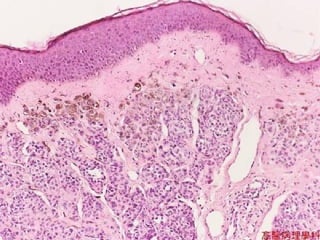

PSORIASIS • 1-2% ofUSA • Elbows, Knees • Parakeratosis, generalized epidermal hyperplasia, elongation of the rete pegs, extensive chronic inflammatory cell infiltrates, “MUNRO” intraepidermal microabscesses

• #77 Name the FOUR histopathologic findings in most of the forms of psoriasis: 1,2,3,4 1) Parakeratosis, 4) hyperplasia, 3) rete peg elongation, 4) MUNRO abscesses.

• #78 Classical psoriasis, parakeratosis, hyperplasia, rete peg elongation, chronic inflammation, microabscesses (of Munro)‏